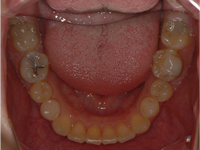

【小学校4年生女児 】拡大装置

「出っ歯」が気になり来院。「できる範囲でお願いします」とのことでした。

難易度 ★★★☆☆ /治療期間 5年 /装置の数 3個

5年後